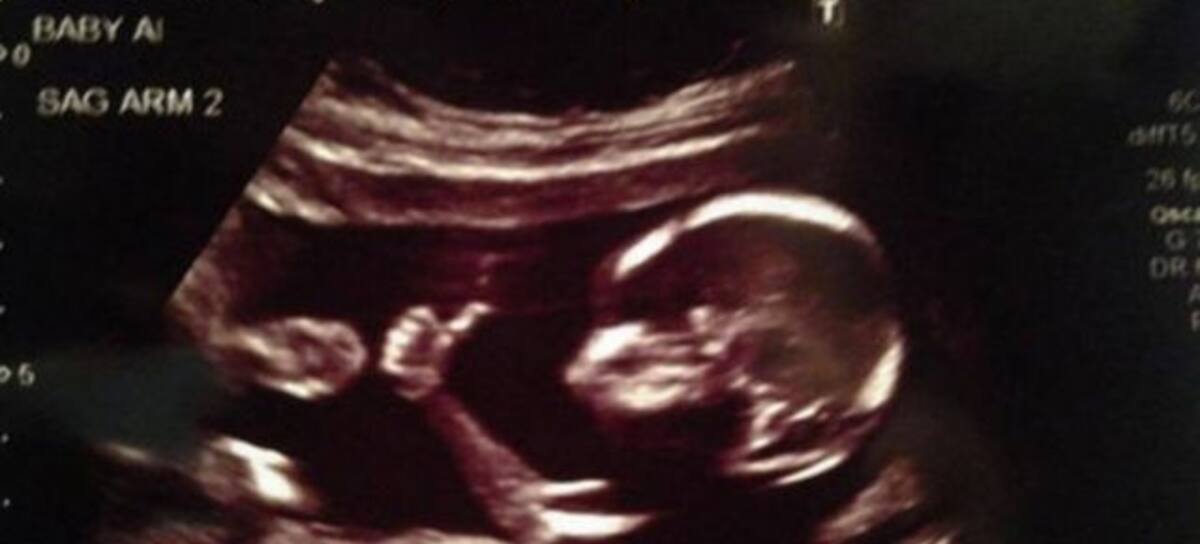

Recientemente se viralizó la historia de una madre en Reddit que compartió dos fotos de su bebé durmiendo, una con 38 semanas de gestación y otra con tres semanas de vida.

Lo que causó curiosidad y ternura entre los internautas es que en ambas fotografías el bebito aparece dormido de la misma manera, con los brazos levantados.